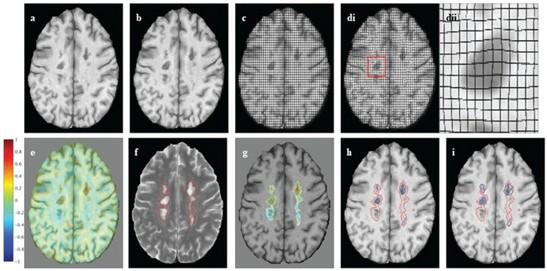

Advanced MRI biomarkers for MS progression

Changes in brainvolume are predictive of clinical and

disability status in CIS, RRMS, and PPMS

Spinal cord atrophy rates in patients with RRMS versus patients who transitioned to SPMS:

mm / year

Patients who developed SPMS showed accelerated spinal cord atrophy rates before conversion compared with their RRMS matches (p<0.0001)

This difference exists at least four years before the conversion to SPMS

Upper cervical cord atrophy, as assessed by MRI, is a predictor of the conversion to SPMS